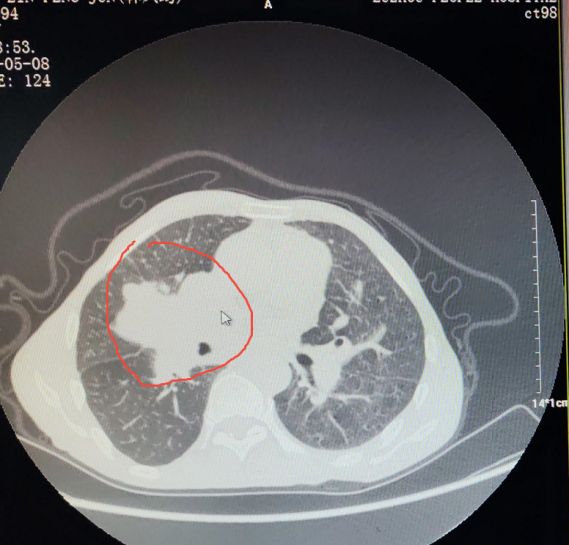

诊断结果确实严峻:右肺中叶鳞状细胞癌晚期,肿瘤已侵犯心包,并转移至双肺、纵隔多处淋巴结。

希望,就在这份坚持中悄然生长。完成六个疗程的化疗后,检查结果令人振奋:CT显示肿瘤病灶明显退缩,左肺转移灶消失。